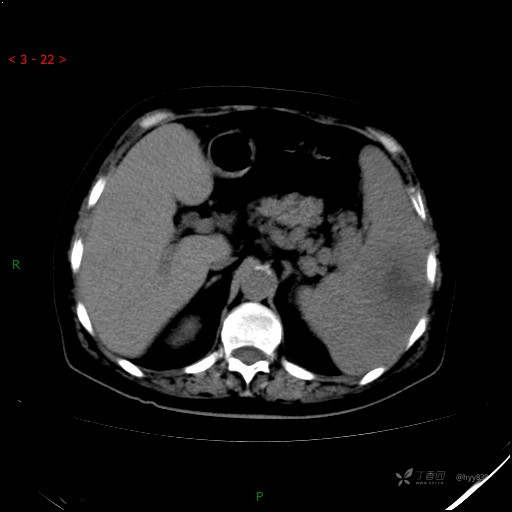

静脉期